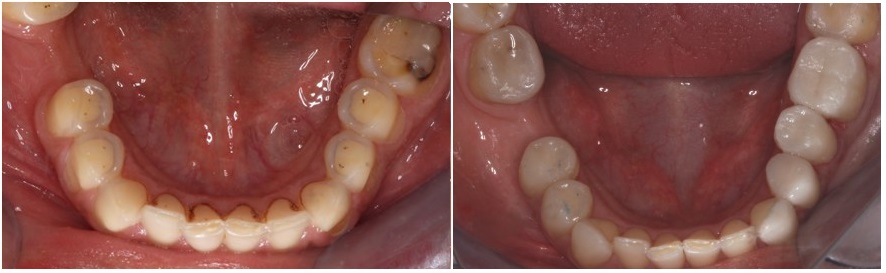

Βλέπετε στην φωτογραφία που ακολουθεί, εικόνα δοντιών με σημαντική διάβρωση που έχει προκληθεί από εμετούς. Στις εικόνες μπορούμε να παρατηρήσουμε τα χαρακτηριστικά της διάβρωσης, όπως το εντονότερο χρώμα των δοντιών στα σημεία όπου χάθηκε η αδαμαντίνη και την αλλαγή της μορφολογίας των δοντιών.

Στις φωτογραφίες που ακολουθούν βλέπουμε την άνω και την κάτω γνάθο γνάθο πριν και μετά την ολοκλήρωση των αποκαταστάσεων.